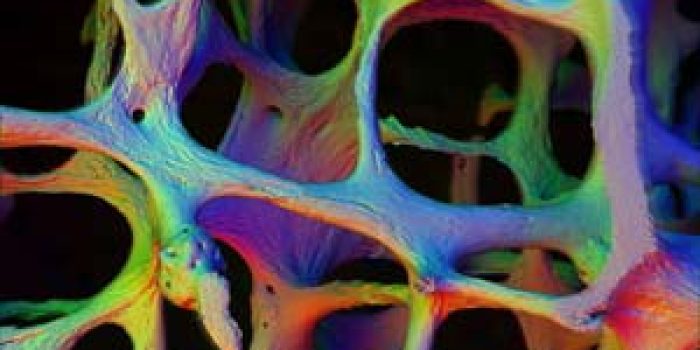

پوکی استخوان یا استئوپروز Osteoporosis به معنی کم شدن تراکم استخوان است که بدنبال آن قدرت استخوان کم شده و شکننده می شود و شکننده شدن استخوان موجب می شود احتمال بروز شکستگی در آن بیشتر شود. پوکی استخوان معمولاٌ بتدریج پیشرفت می کند و هیچ علامتی از خود بروز نمی دهد تا وقتی که شکستگی بوجود می آید. پوکی استخوان می تواند در هر استخوانی از بدن ایجاد شود ولی معمولا در ستون مهره، لگن، مچ دست و دنده ها بیشتر دیده می شود.